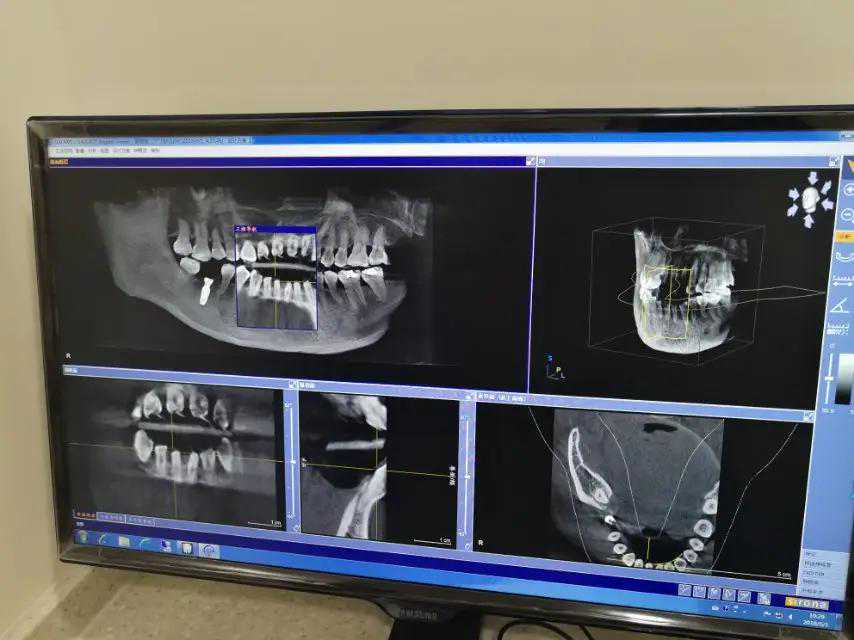

种牙前,一定要看硬件设备是否齐全,硬件设备决定了医疗机构的专业度以及可治疗的范围;

所以如果你是想做种植牙,但机构没有放射诊疗资质,基本上可以不用考虑了,因为不拍CT是无法诊断口腔疾病情况的。

怎么判断一个医疗机构能否拍牙片呢?最简单的做法是看放射诊疗许可!

医疗机构开展放射诊疗活动必须取得《放射诊疗许可证》。